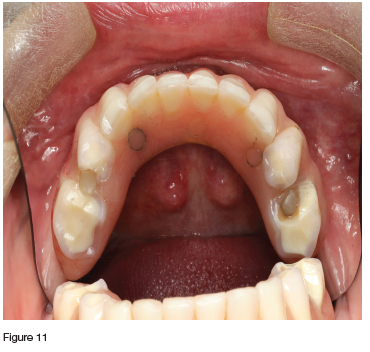

In the maxilla, the porcelain prosthesis remained intact with no fractures for 13 years (figures 8 & 9), however there was a single event of cement failure (figure 10) at year 12 in 2022. This event was easily managed through sandblasting the intaglio surface of the FPD and re-cementing it. The mandibular acrylic prosthesis also remained intact and functional for over 13 years, but did exhibit ±2.5 mm occlusal wear during this time. Additionally at year seven (2019) and year ten (2022) it had two separate events requiring replacement of the screw access hole closure material which had been lost (figures 9 & 11). No implant or framework complications were observed, nor was there any noticeable bone loss in either the maxilla or mandible (figure 8). The patient reported high satisfaction with both her aesthetics and chewing efficiency.

The 13-year success of the maxillary telescopic crown-retained PFM prosthesis (for aesthetics) and mandibular acrylic veneered hybrid prosthesis (for function) aligns with biomechanical principles. The mandibular prosthesis exhibited moderate occlusal wear (±2.5 mm over 13 years), necessitating two minor repairs. It may be argued that there is a need for the complete replacement of the veneering material, but in this instance, the patient was not keen to be without her prosthesis, and thus the wear was managed with minimal intervention, and the prosthesis was repaired and not replaced. The wear was anticipated as it aligns with studies showing acrylic's susceptibility to wear compared to porcelain, with average wear rates of 0.2-0.3 mm annually under functional loading.5 The rate may have been accelerated in her case due to the harder porcelain material in the opposing arch. Acrylic's reduced wear resistance is a well-documented trade-off for its shock-absorbing properties, which protect implants from overload and potential peri-implant bone loss.3,6 Notably, a four or five-implant support system distributed forces effectively, preventing framework fractures or implant mobility despite wear, consistent with protocols advocating >4 implants for cantilevered prostheses.2,4 The loss of screw access hole closure material in the fourth quadrant was a minor complication, and has also been reported in the literature to occur in 15-20% of screw-retained hybrid prostheses over time.5,8 These issues are attributed to cyclic masticatory forces and do not indicate prosthetic failure but rather routine maintenance needs.7